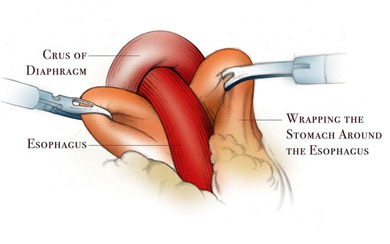

Scopul interventiei chirurgicale este de a restabili bariera antireflux, fără a crea obstacole în calea bolului. Nissen fundoplicatură - chirurgie antireflux, în care folie gastric în jurul părții inferioare a esofagului 360 °. creând o manșetă care previne conținutul gastric în esofag. Inainte de operatie, pacientii ar trebui sa fie examinate cu atenție, o atenție deosebită trebuie acordată la ultimul etaj al radiografiei tractului gastro-intestinal pentru a exclude alte posibile boli.

Principalele etape ale fundoplicatură Nissen:

- mobilizarea fundus gastrice și cardia;

- crearea tunelului din spatele esofagului;

- efectuarea de fundus a stomacului in spatele esofagului;

- creând un drum liber Nissen înălțime manșetă de 1 - 2 cm;

- fixarea manșeta la esofag și piciorul drept al diafragmei;

- excizia sacul herniei și suturarea diafragmei la picioarele HH.

Manșetă Nissen reticulat pe două rânduri sutura.

Realizarea fundus a stomacului in spatele esofagului